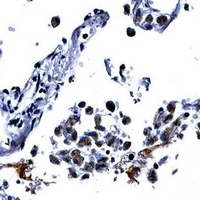

Immunohistochemical analysis of IL-13 staining in human lung formalin fixed paraffin embedded tissue section. The section was pre-treated using heat mediated antigen retrieval with sodium citrate buffer (pH 6.0). The section was then incubated with the antibody at room temperature and detected using an HRP conjugated compact polymer system. DAB was used as the chromogen. The section was then counterstained with haematoxylin and mounted with DPX. Immunohistochemical analysis of IL-13 staining in human lung formalin fixed paraffin embedded tissue section. The section was pre-treated using heat mediated antigen retrieval with sodium citrate buffer (pH 6.0). The section was then incubated with the antibody at room temperature and detected using an HRP conjugated compact polymer system. DAB was used as the chromogen. The section was then counterstained with haematoxylin and mounted with DPX.